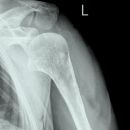

Schulter a.-p. (chirurgisch)

Technik

• FDA: 1,15 m

• Ausgangsformat: 24/30 hoch

• mit Raster

Indikation

Fraktur, Luxation, Osteosynthesematerial

Lagerung

sitzend/ stehend aufrecht am Rasterwandstativ

nicht aufzunehmende Seite um 45° anheben

Hand in Supination, Arm leicht abspreizend

Zentralstrahl

Querstrahl: ergibt sich durch 2 QF Licht über Schulter-Haut-Grenze

Längsstrahl: über Gelenkspalt

evtl. Tiefenblende anpassen

Anmerkung

Unfall-Patienten - Aufnahme auch im Liegen möglich

Qualitätskriterien

Gelenkfläche der Scapulapfanne (Glenoidal-Gelenk) soll strichförmig abgebildet sein, der Humerus soll frei projiziert werden. Die Aufnahme kann mit der Rockwood-Aufnahme kombiniert werden (Röhrenkippung). evtl. Schulterfilter verwenden.

- vollständige überlagerungsfreie Darstellung des Humeruskopfes und des Gelenkes